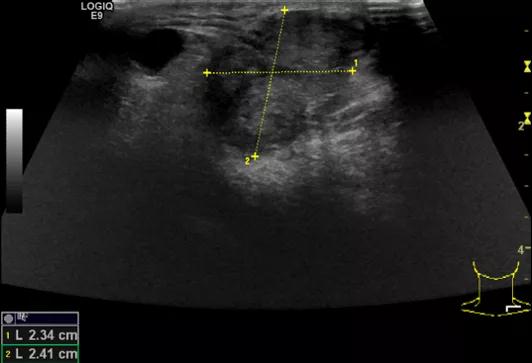

第四例是胸腺癌化妆包,术后、化疗之后淋巴结转移,肿块范围巨大,99mm*61mm,边界不清,呈浸润状,肿块包绕颈动脉,颈内静脉压闭,症状明显。由于患者放化疗也不敏感、血供非常丰富,于是采取多点姑息性消融。姑息性消融后未实现完全消融,病灶大片坏死,肿胀疼痛得到明显的缓解,后续患者未再来复查。

(病例4图例)